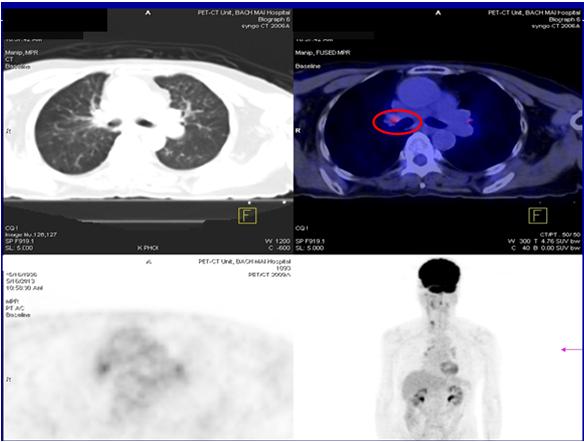

* Bệnh nhân được tiến hành chụp PET/ CT đánh giá giai đoạn bệnh:

Kết quả cho thấy: Thùy trên phổi phải có khối kích thước 2x4cm, tăng hấp thu FDG, max SUV: 12,6. Nhiều nốt tổn thương 2 phổi, tăng nhẹ hấp thu FDG, max SUV: 2,5. Không phát hiện hạch trung thất và các tổn thương tại cơ quan khác.

Hình 1: Hình ảnh khối u đỉnh phổi phải và các tổn thương thứ phát tại hai phổi trên phim chụp PET/ CT